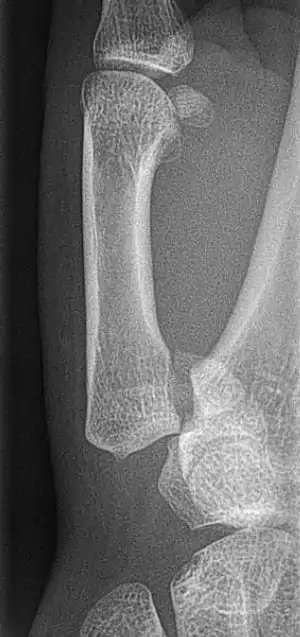

Bennett fracture is a fracture of the base of the first metacarpal bone which extends into the carpometacarpal (CMC) joint.[1] This intra-articular fracture is the most common type of fracture of the thumb, and is nearly always accompanied by some degree of subluxation or frank dislocation of the carpometacarpal joint.

Though these fractures commonly appear quite subtle or even inconsequential on radiographs, they can result in severe long-term dysfunction of the hand if left untreated. In his original description of this type of fracture in 1882, Bennett stressed the need for early diagnosis and treatment in order to prevent loss of function of the thumb CMC joint, which is critical to the overall function of the hand.[3]